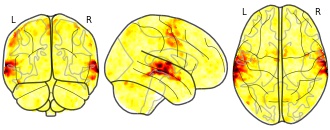

EmailClick to copy linkLink copied Cite(2020). Individual Brain Charting dataset extension, second release of high-resolution fMRI data for cognitive mapping: sub-04_ses-12_task-mtt_sn_dir-pa_run-01_sn_northside_event [Dataset]. http://identifiers.org/neurovault.image:364810niftiAvailable download formatsUnique identifierhttps://identifiers.org/neurovault.image:364810Dataset updatedFeb 14, 2020License

Cite(2020). Individual Brain Charting dataset extension, second release of high-resolution fMRI data for cognitive mapping: sub-04_ses-12_task-mtt_sn_dir-pa_run-01_sn_northside_event [Dataset]. http://identifiers.org/neurovault.image:364810niftiAvailable download formatsUnique identifierhttps://identifiers.org/neurovault.image:364810Dataset updatedFeb 14, 2020LicenseCC0 1.0 Universal Public Domain Dedicationhttps://creativecommons.org/publicdomain/zero/1.0/

License information was derived automaticallyDescriptionCollection description

The individual Brain Charting (IBC) Project is using high resolution fMRI to map 13 subjects that undergo a large number of tasks: the HCP tasks, the so-called ARCHI tasks, a specific language task, video watching, low-level visual stimulation etc. The native resolution of the data is 1.5mm isotropic. Their main value lies in the large number of contrasts probed, the level of detail and the high SNR per subject. This dataset is meant to provide the basis of a functional brain atlas. We upload here smoothed individual SPMs. The uploaded maps comprise session-specific and fixed effects across maps acquired with AP and PA phase encoding directions.

Note that Neurovault collection #4438 is a subset of that one. In the present collections, some details have been fixed, including mroe accurate and unique file naming.

Subject species

homo sapiens

Modality

fMRI-BOLD

Analysis level

single-subject

Cognitive paradigm (task)

Mental time travel task

Map type

Z

- d